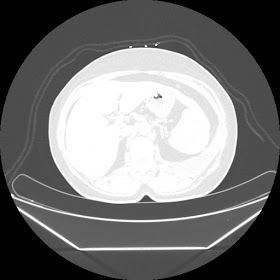

A 45 years old woman recurrent HRCT Images